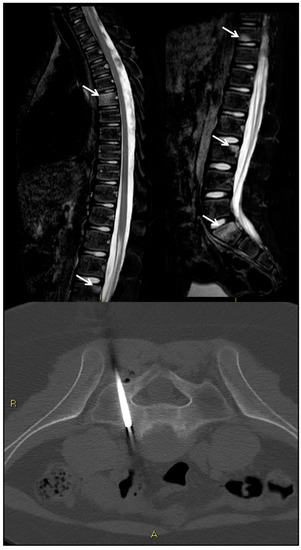

9. Spondylodiscitis

- Michel, S.C.; Pfirrmann, C.W.; Boos, N.; Hodler, J. CT-guided core biopsy of subchondral bone and intervertebral space in suspected spondylodiskitis. AJR Am. J. Roentgenol. 2006, 186, 977–980. [Google Scholar] [CrossRef] [PubMed]

- Rimondi, E.; Rossi, G.; Bartalena, T.; Ciminari, R.; Alberghini, M.; Ruggieri, P.; Errani, C.; Angelini, A.; Calabrò, T.; Abati, C.N.; et al. Percutaneous CT-guided biopsy of the musculoskeletal system: Results of 2027 cases. Eur. J. Radiol. 2011, 77, 34–42. [Google Scholar] [CrossRef]

- Jevtic, V. Vertebral infection. Eur. Radiol. 2004, 14 (Suppl. 3), E43–E52. [Google Scholar] [CrossRef]

- Berbari, E.F.; Kanj, S.S.; Kowalski, T.J.; Darouiche, R.O.; Widmer, A.F.; Schmitt, S.K.; Hendershot, E.F.; Holtom, P.D.; Huddleston, P.M.; Petermann, G.W.; et al. 2015 Infectious Diseases Society of America (IDSA) Clinical Practice Guidelines for the Diagnosis and Treatment of Native Vertebral Osteomyelitis in Adults. Clin. Infect. Dis. 2015, 61, e26–e46. [Google Scholar] [CrossRef] [PubMed] [Green Version]